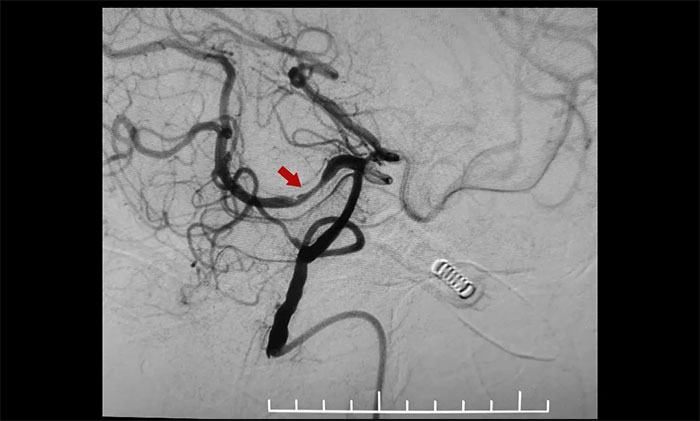

患者为老年男性,因脑梗加重入院。脑血管造影显示,右侧大脑中动脉M1段闭塞、右侧大脑后动脉P1、P2交界段重度狭窄。并且,患者血管条件差、迂曲明显、责任血管纤细,手术极其容易出现出血,局部血栓形成等风险,手术难度不言而喻。

术中,通过输送型球囊扩张微导管轻松越过狭窄病变,完成右侧大脑后动脉狭窄段的球囊扩张及支架置入等步骤,无需进行微导管交换、球囊交换以及支架微导管交换的过程。手术治疗部分仅耗时30分钟。术后造影显示右侧大脑后动脉P1、P2交界段重度狭窄明显改善。行支架CT见支架成形良好。

▲ 术前,右侧大脑后动脉重度狭窄